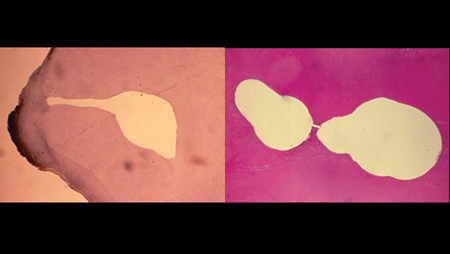

Endodontics became a dental specialty in 1964. At its very beginning, endodontics’ idea of the Triad was revelatory, as was the deep commitment to it. Even in the age before NiTi, microscopes, apex locators, and digital imaging, careful and vigilant attention to technical detail produced verifiable success.3,4 It has been said many times before that we stand on the shoulders of giants, and now future giants stand on our shoulders today. (Fig. 1)

Fig. 1A

Fig. 1B

Fig. 1C

Fig. 1D